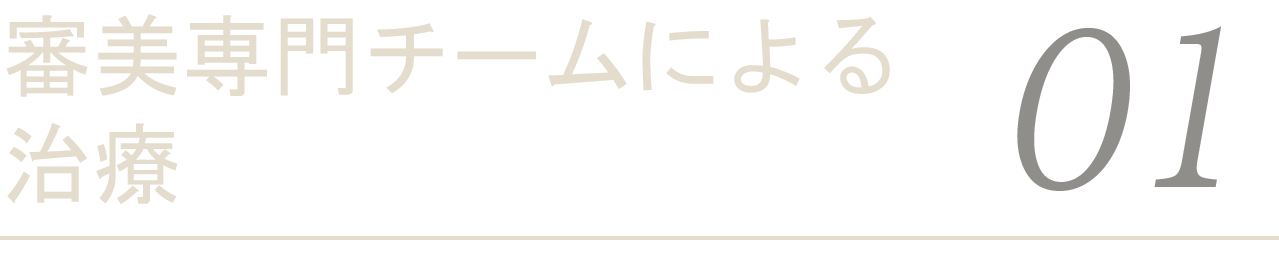

型取りの際、歯の根元周囲に糸を巻き歯茎を離す「歯肉圧排」を行うことで、歯茎との境目が正確に反映され、歯科技工士がより精巧に人工歯を作ることが可能となります。

手間がかかる作業ですが、審美性を追求するには必要な作業と考えています。

歯の型を取る際、一般的に安価なピンク色の素材を使いますが、当医院の審美歯科では高品質な「シリコン素材」を重ねて使用しています。

割高な素材ですが、歪みが少なく正確に型を採取でき、歯と人工歯の接着度(適合)が高まります。

歯の根元の型を精密に取れるようにするため、歯と茎の間に糸を入れていきます。

続いて太い糸を歯と茎の間に入れていきます。

保険治療では使えない、高品質のシリコン素材を使用して正確な型取りを行います。